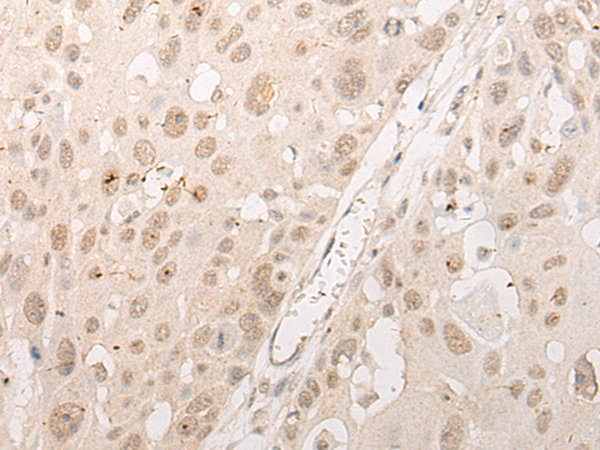

分类: 科研抗体货号: P02569别名: CPSF160; P/cl.18; HSU37012应用: IHC反应种属: Human, Mouse